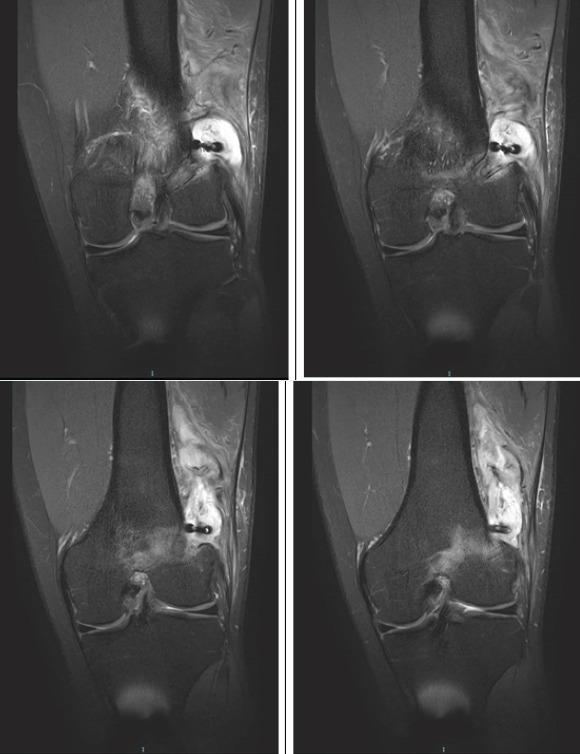

Our patient presented 6 months post-ACL reconstruction, with a large swelling over the lateral aspect of the femur in the operated knee. His presentation presented a clinical dilemma: On the one hand, he presented with a large cystic swelling adjacent to the knee, but had only vague knee pain with no significant joint effusion and no fever or other constitutional symptoms; while on the other, his swelling was significantly large and his imaging findings were worrisome. This cystic swelling turned out to be an infected cyst arising from the tissue adjacent to the femoral tunnel. We present a rare complication of ACL reconstruction and discuss the possible causes of such large cystic swellings. We also discuss the management of large infected cysts post-ACL reconstruction.

我们的患者在ACL重建术后6个月,手术膝关节的股骨外侧出现一个巨大肿胀。他的情况带来了临床难题:一方面,他在膝关节附近有一个巨大的囊性肿胀,但仅有模糊的膝关节疼痛,无明显关节积液,也无发热或其他全身症状;另一方面,他的肿胀非常大,影像学检查结果令人担忧。这个囊性肿胀原来是一个源自股骨隧道附近组织的感染性囊肿。我们报告了ACL重建的一种罕见并发症,并讨论了这种巨大囊性肿胀的可能原因。我们还讨论了ACL重建术后巨大感染性囊肿的处理方法。